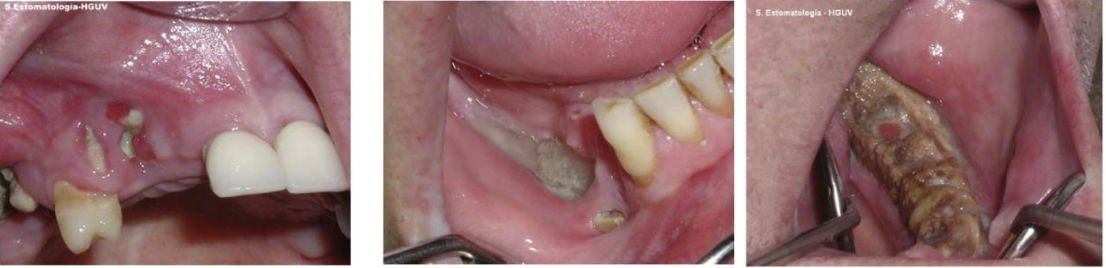

Sialolithiasis (唾液腺結石症) | 和鈣、磷的代謝無關 | Submandibular gland | - |

![]() |

|||

Sialadenosis (Sialosis,唾液腺腫大) | 治療效果不好,除非控制住潛在的系統性疾病 | ||||||

Xerostomia (dry mouth,口乾症) | - | 舌乳頭萎縮、鵝口瘡(oral candidiasis), 蛀牙 ![]() |